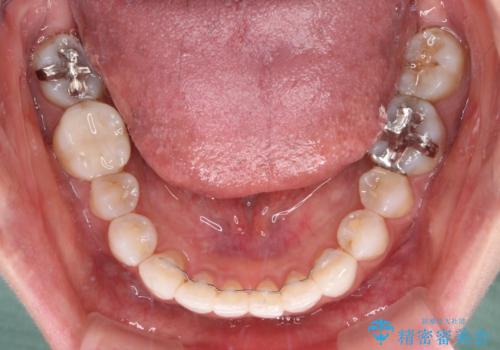

- 前歯のデコボコを気にして来院された患者様です。

歯列不正が軽度であり、インビザラインの装着時間を遵守してくださったため、日本と海外を行き来しながらも2年弱でしっかりと仕上げることができました。